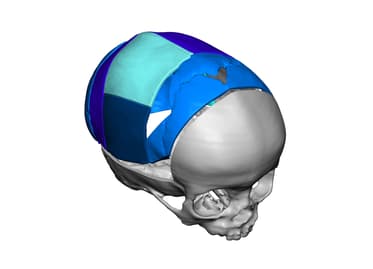

Comparison of subcutaneous pocket with cryopreservation, VSP Craniomaxillofacial Solutions | 3D Systems

VSP Craniomaxillofacial Solutions | 3D Systems大東流秘伝大鑑 著者 曽川和翁